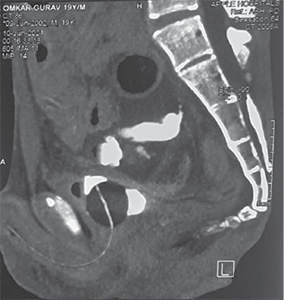

He was resuscitated with 1 500 ml of crystalloids through a left subclavian central line. Contrast-enhanced CT of the abdomen revealed perforation of the urinary bladder and extravasation of free urine into the pelvic cavity. It also revealed pneumointestinalis and grossly dilated bowel loops till mid transverse colon. There was a cut-off point at the level of the mid transverse colon (Figure 1).

Figure 1. Contrast enhanced computed tomography abdomen pelvis showing A – axial view showing dilated ascending colon, proximal transverse colon, intraperitoneal fluid collection B – extravasation of urine inside peritoneal cavity with pelvic collection